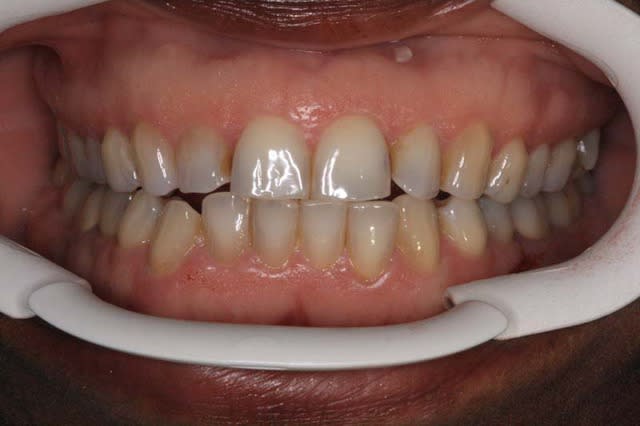

c‘est un cas que j’ai vu ce matin

La patiente (66 ans) se plaint de douleurs au niveau de l’A.T.M.

Gouttières ou ?

Pourtant y'a tous les critères de Planas, Md carrée, facettes d'usure, pas de protection canine ( semble-t'il)donc elle devrait pas souffrir, c'est une simulatrice!

P.S.: ce qui est remarquable est qu'il y beaucoup de critères de Planas

Occlusion imparfaite : presque ne bord à bord au niveau incisal

12 : usure ++

perte des protections canines

pas de mylolyse

peu d'usure indiquant un bruxisme horizontal

pas de 8 max sur les photos mais présence de 8 mandibulaires

> interférence des 48/38 avec les 17/27 ?

Au niveau dentodentaire la situation si elle n'est pas idéale n'est pas catastrophique.